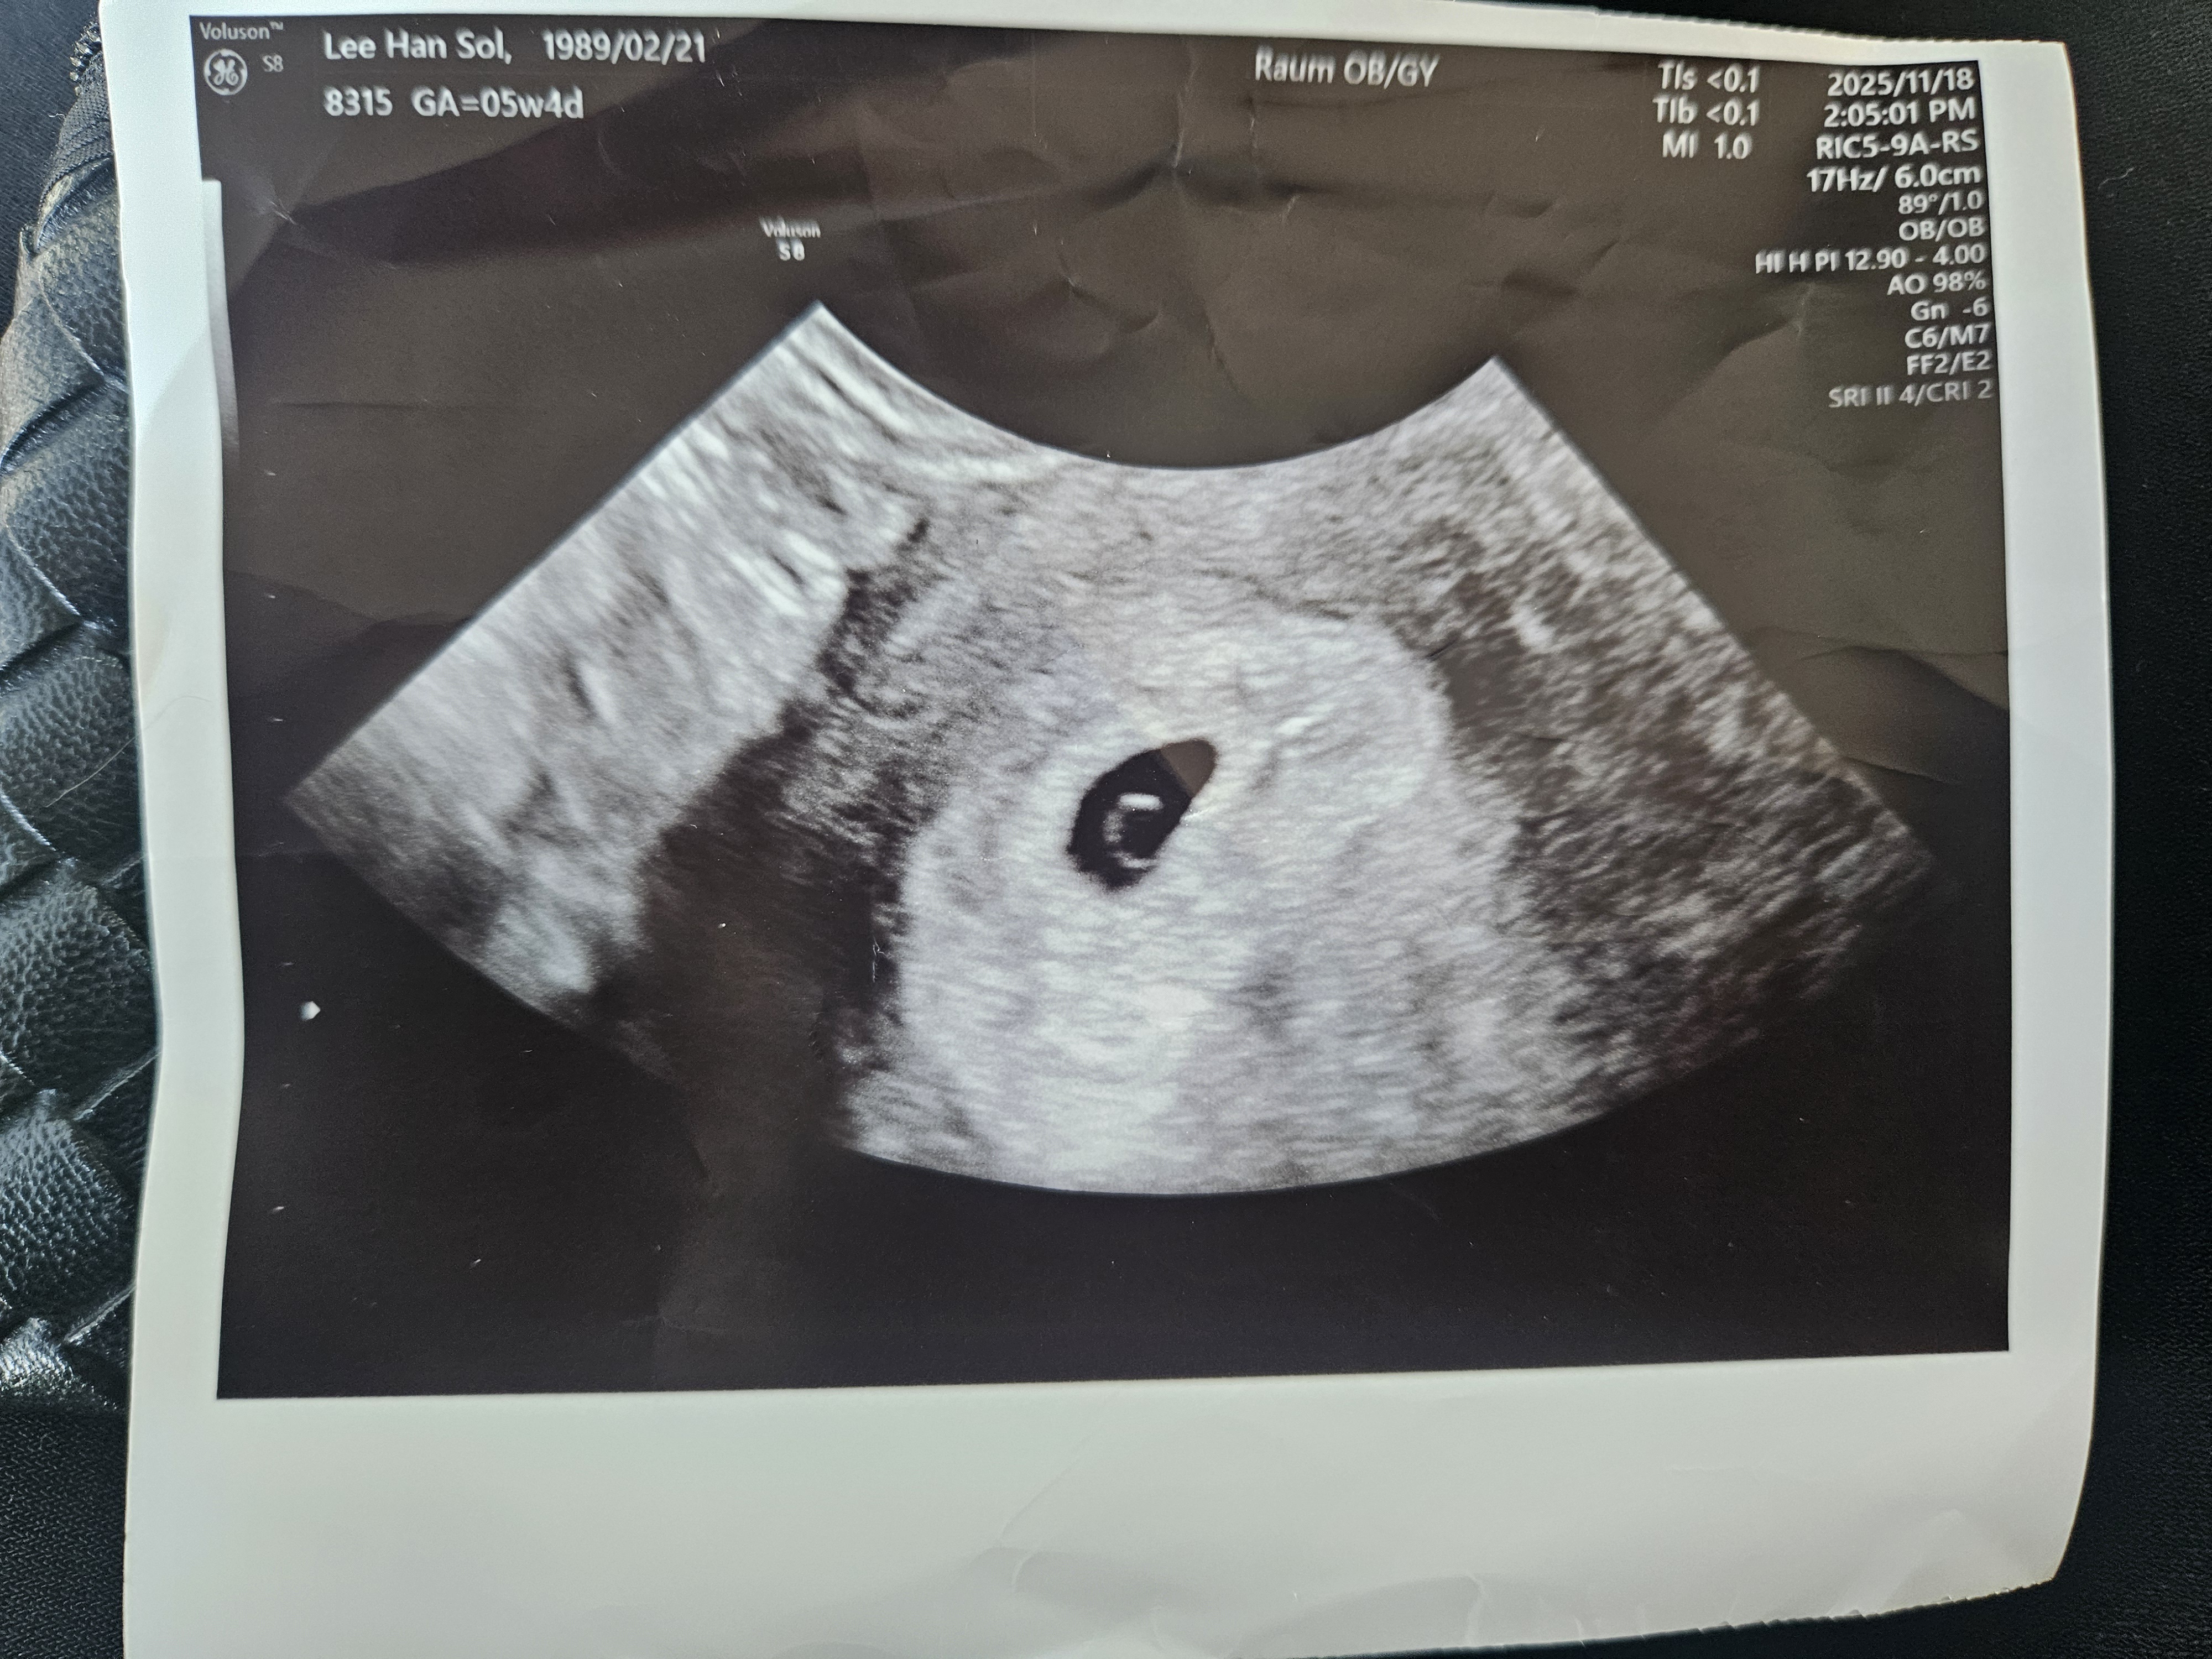

5주4일차인데 난황이 좀 큰것같아요

어떻게 보이세요??... 쌤께서는 별말씀 없으시긴 했는데 비슷한 주수의 촘파사진들 보면 난황이 평균크기거나 작거나 그런것같은데ㅠㅠ 별말씀 안하시고 2주후에 보자하셨으니 괜찮겠죠? 늦은나이에 첫임신이라 하나부터 열까지 다 걱정핑 불안핑이네요 ㅠㅠㅋㅋㅋ

저는 커서 ㅋㅋ 선생님이 난황이 아주 크고 건강하게 잘크고있다 말씀해주셨습니다! 잘기다려서 우리 얼른 애기심장소리도 들어요!

초음파 각도에따라 보이기도 안보이기도 크게보이기도 작게보이기도 하고 그렇더라고요 ~~ 애기도 마찬가지고요